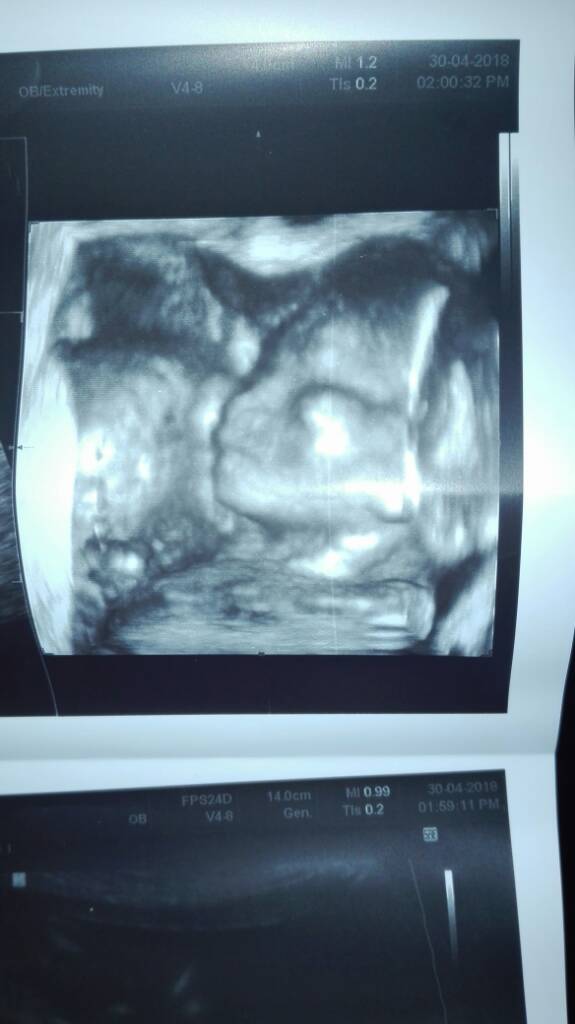

Nie wiem czy też to zobaczycie ale to twarz mojego drugiego synka :) :)

Na wizycie wszystko ok...ufff

Usg zaplanował na 28.05Zobacz załącznik 852189